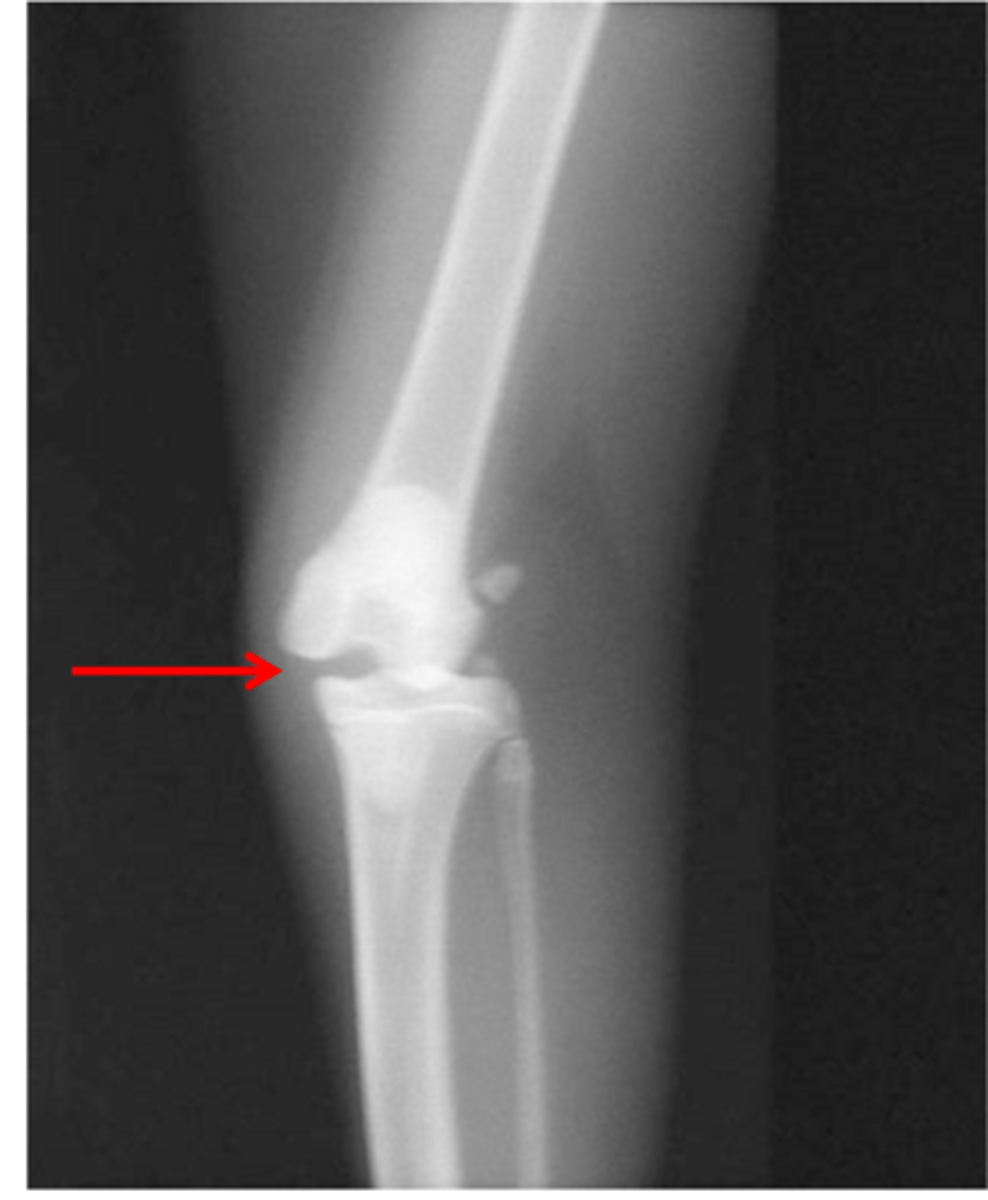

stress RAD of cat with MCL injury

what is shown in this image